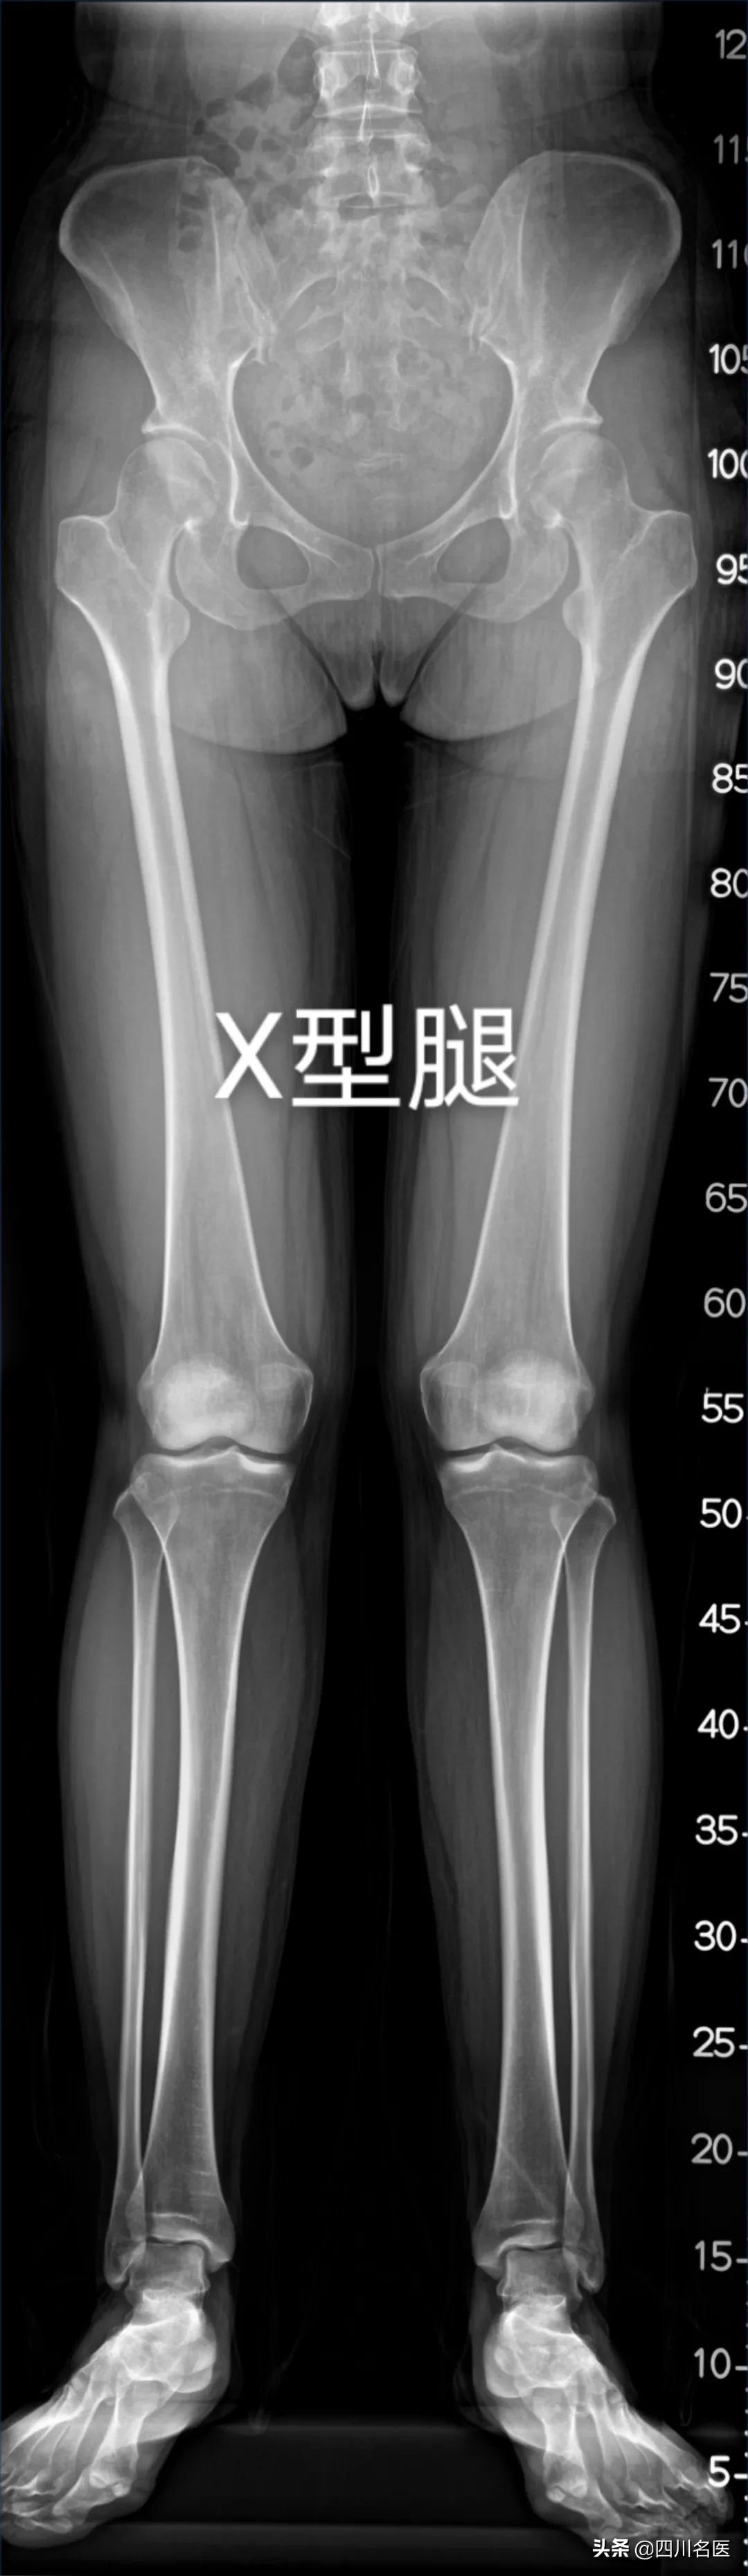

但也有一部分人的双下肢呈O型或者X型,医学上称之为膝内翻 (O型腿)、膝外翻(X型腿), 也就是通常所说的O型腿或X型腿。

闵鹏医生介绍:医学上对于膝内翻、膝外翻的诊治和研究,是以 下肢机械力线 (以下简称下肢力线) 为基础,就是从股骨头中心到踝关节中心画一条直线:

▷如果正常腿是直的情况下,这条直线通过膝关节中心 (图①) ;

▷ 对于膝内翻,这条直线偏于膝关节中心点的内侧(图②) ;

▷ 对于膝外翻,这条直线偏于膝关节中心点的外侧(图③) 。

图片来源:美国巴尔的摩Sinai国际肢体延长中心

而这需要专科医生通过问询,查体和标准的双下肢全长X光片综合判断,所以大家别再焦虑了,你认为的腿弯,可能真的不弯。